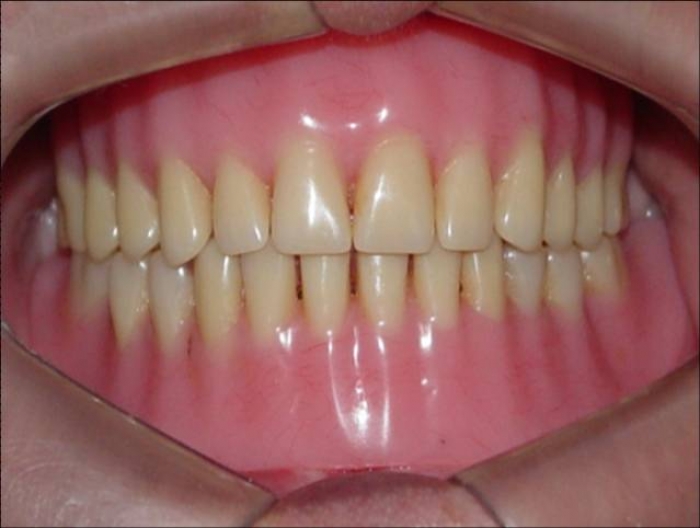

Imagem inicial

Sorriso inicial